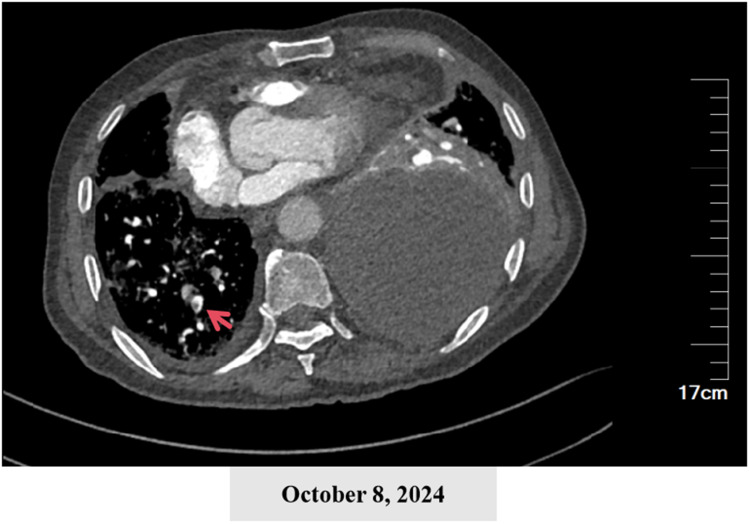

Case presentation: We report a 77-year-old male with a history of chronic smoking and alcohol consumption who presented with a two-month history of cough, sputum production, and progressive dyspnea. His condition rapidly deteriorated with high fever and respiratory failure. Initial antibiotic therapy was ineffective, and multiple cultures of blood, sputum, and pleural fluid were negative. However, mNGS of blood and pleural fluid identified Porphyromonas gingivalis, a well-known periodontal pathogen rarely associated with pulmonary infections. The patient's treatment was adjusted to include targeted anaerobic coverage (imipenem plus vancomycin) alongside chest tube drainage, leading to significant clinical improvement.